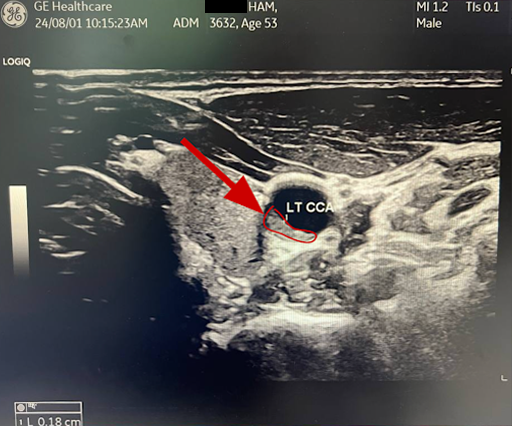

Before: RT CCA . Longitudinal . Baseline

Before: LT CCA . Longitudinal . Baseline

After: Plaque remodeling and reversal. B-mode ultrasound imaging of the carotid artery. Kevin Ham, MD, 2025. Three months on the CAST protocol: WFPB diet, high-intensity cycling, structured fasting, targeted supplementation.